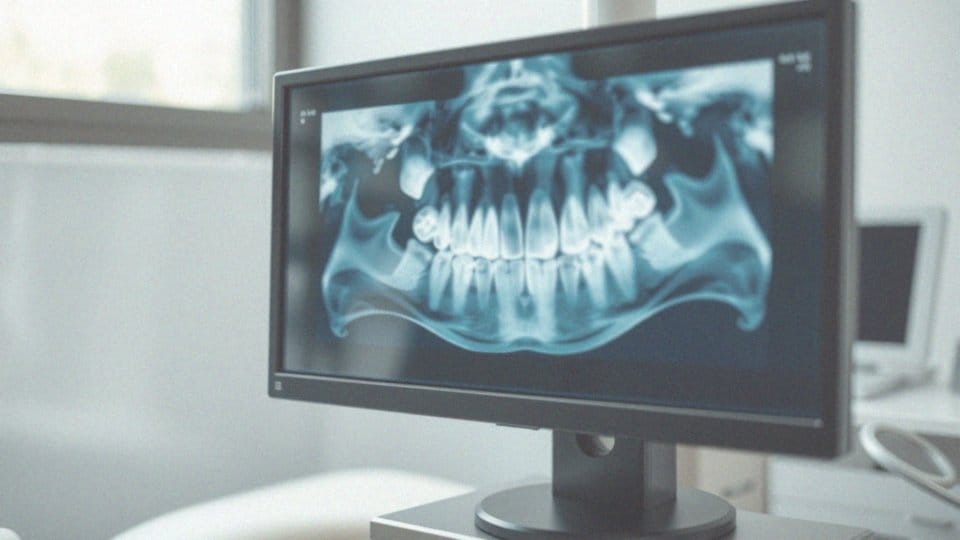

Zatrzymana ósemka, czyli ząb mądrości, to sytuacja, gdy ząb ten nie wyrasta w pełni lub jest źle ustawiony w jamie ustnej. Często taka sytuacja ma miejsce z powodu braku wystarczającej przestrzeni w łuku zębowym, co uniemożliwia prawidłowy rozwój tego zęba. W efekcie, ząb może utknąć w kości szczęki lub pod dziąsłami, co prowadzi do:

Jakie metody leczenia są stosowane w przypadku zatrzymanej ósemki?

Leczenie zatrzymanej ósemki w dużej mierze zależy od stopnia jej zatrzymania oraz od towarzyszących objawów. Jeśli ząb nie sprawia bólu, stomatolog może ograniczyć się jedynie do regularnego monitorowania sytuacji. W przypadku wystąpienia dolegliwości bólowych lub stanów zapalnych wprowadza się leczenie zachowawcze. Generalnie polega ono na stosowaniu środków przeciwbólowych oraz leków przeciwzapalnych. Jednak gdy obecność ósemki prowadzi do poważniejszych problemów, niekiedy konieczne staje się leczenie chirurgiczne.

Ekstrakcja zęba mądrości jest jednym z takich rozwiązań, a jej metody mogą być różnorodne:

- Ekstrakcja prosta – kiedy ząb jest całkowicie widoczny, usunięcie go jest prostsze.

- Dłutowanie – tę metodę stosuje się, gdy ząb jest częściowo lub całkowicie zatrzymany, co wymaga rozbicia kości wokół niego.

- Nacięcie dziąsła – ta technika jest pomocna, gdy ząb znajduje się głęboko i wymaga nacięcia tkanki miękkiej.

- Dekapiszonaż – używana w przypadku, gdy wokół zęba znajduje się zwiększona ilość tkanki.

Czasami potrzeba również leczenia ortodontycznego, aby zapewnić odpowiednią przestrzeń dla zęba, co zmniejsza ryzyko komplikacji. Regularne wizyty u dentysty są niezwykle istotne, ponieważ pozwalają na bieżąco śledzić stan zębów oraz szybko wprowadzać konieczne leczenie.